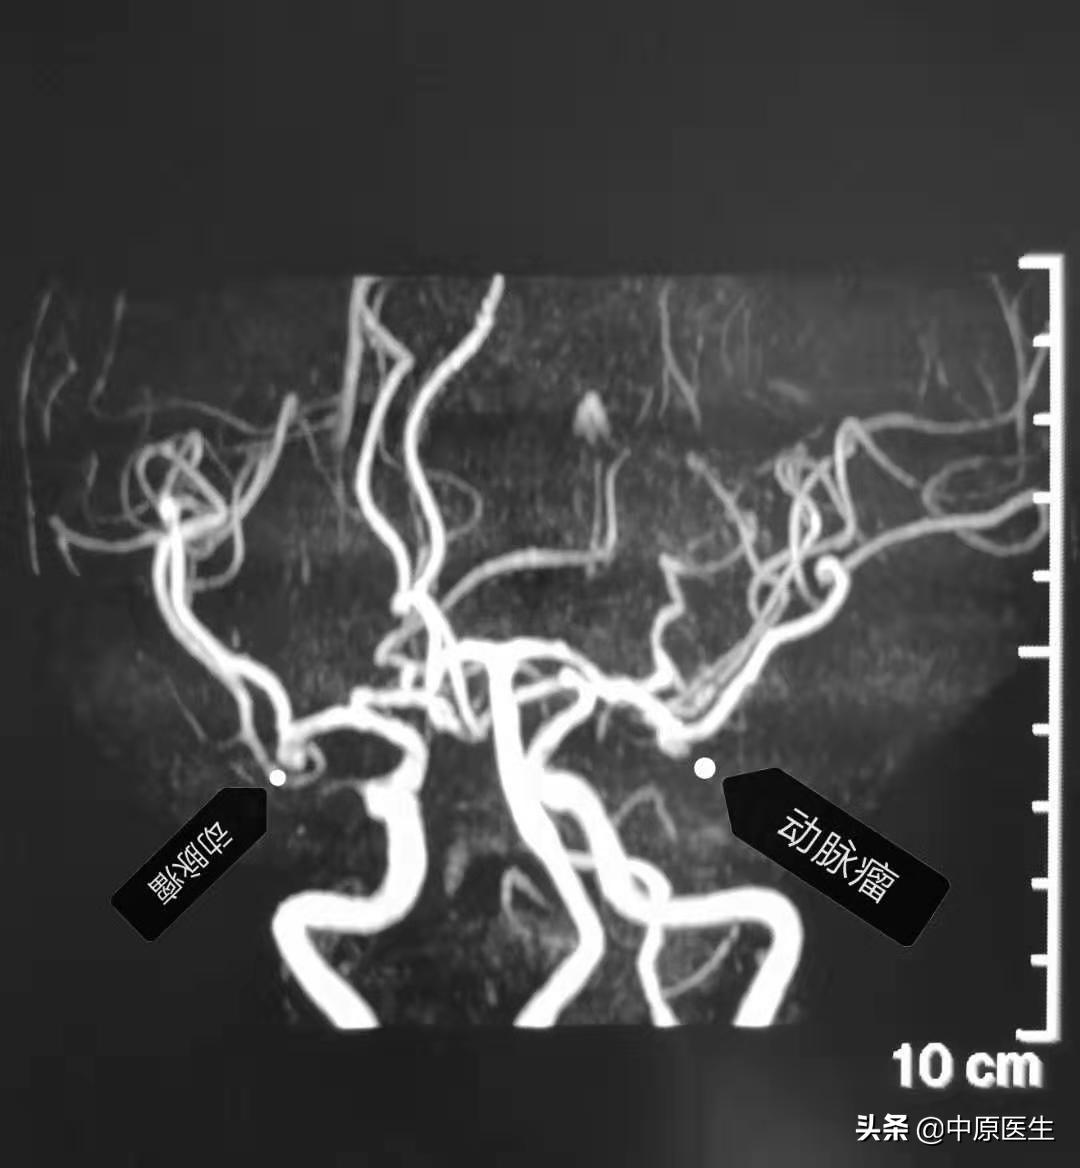

一个老人体检大脑里发现两个动脉瘤,(见图1)然后来看我的门诊。

血管曲里拐弯儿,可把赵小源难为坏了。(见图2~6)